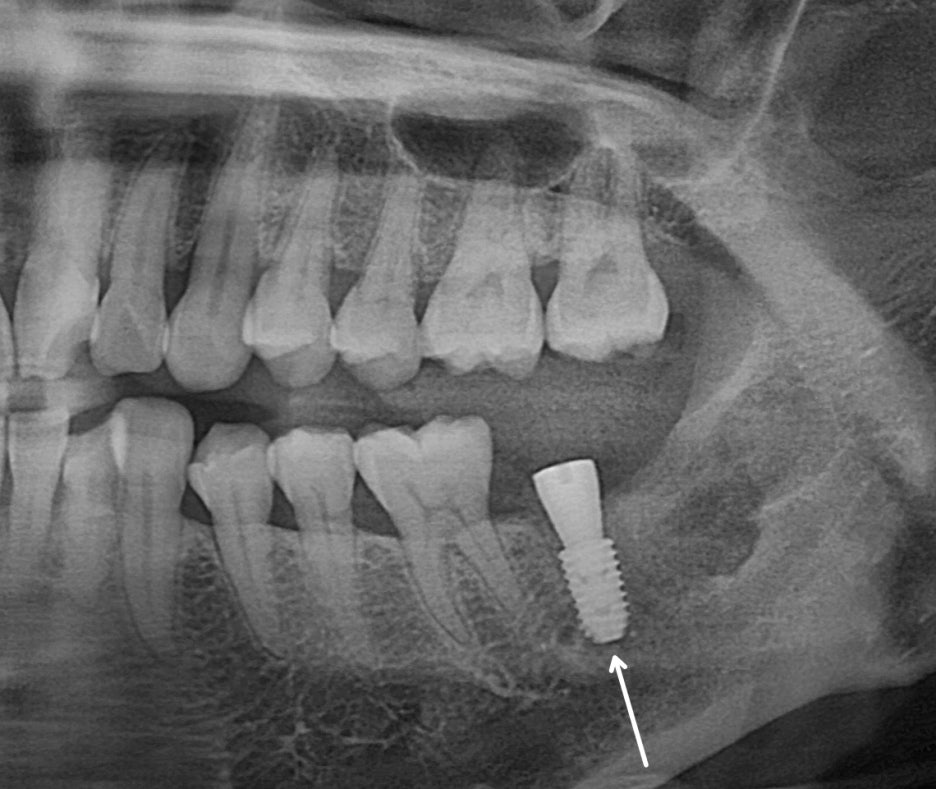

민락 치과 에서 보여드리는

술후 엑스레이를 확인해 보면

잇몸 치료를 병행했기 때문에

전반적으로 치석도 제거되었으며,

임플란트 역시 잘 식립되어 있습니다.